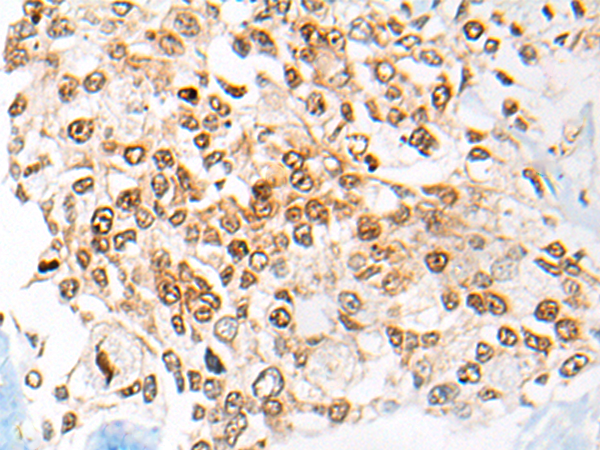

分类: 科研抗体货号: P02473别名: CPR4应用: WB,IHC反应种属: Human